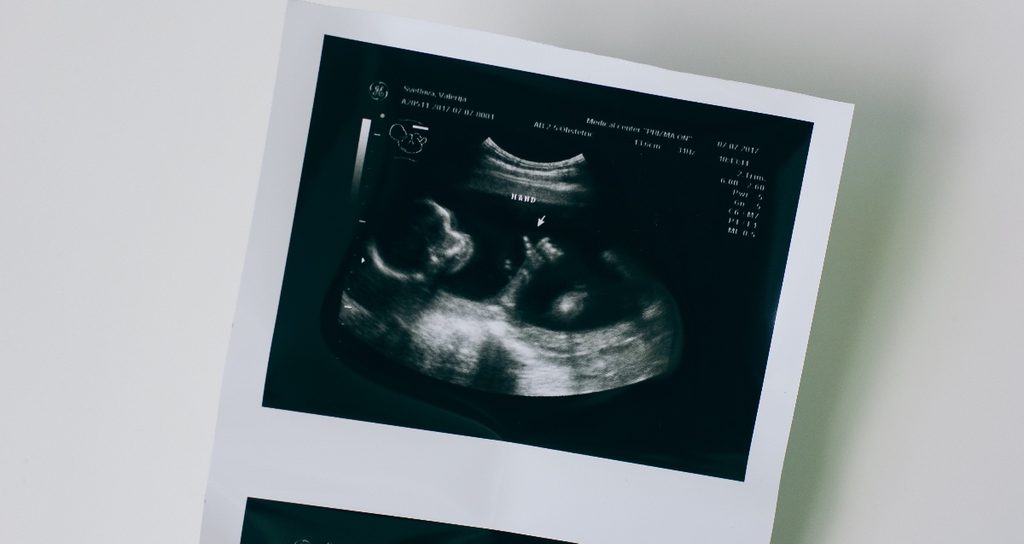

- الفحوصات الطبية: استشارة الطبيب وإجراء الفحوصات الدورية تساهم في متابعة تطورات الحمل.